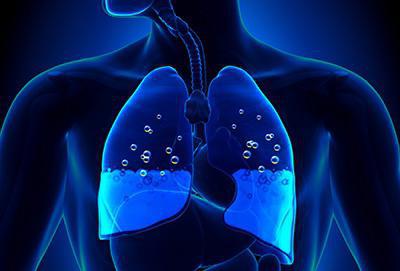

Отек легких (ОЛ) – это клинический синдром, связанный с накоплением излишней жидкости в интерстициальной ткани и/или альвеолах и проявляющийся нарушениями процесса газообмена в легких, ацидозом (смещением кислотно-щелочного резерва крови в кислую сторону) и гипоксией органов и тканей.

В основе патологического механизма развития основную роль играют нарушения проницаемости мембраны между альвеолами и капиллярами, снижение коллоидно-осмотического и увеличение гидростатического давления в сосудах микроциркуляторного русла.

В начальной стадии происходит пропотевание транссудата в интерстициальную легочную ткань. Избыточное его накопление и обуславливает развитие сердечной астмы (интерстициального отека легких).

Дальнейшее нарастание отечности тканей способствует проникновению транссудата в полость альвеол, где он смешивается с воздухом с образованием пены. Эта пена и препятствует нормальному газообмену. Данная стадия называется альвеолярным отеком.